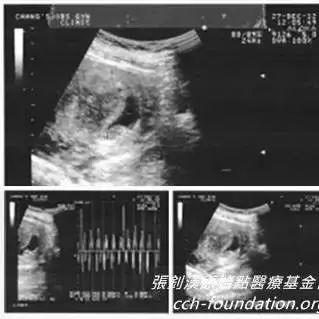

学员原始点应用与处理过程: 我是原始点台北志工 2014年2月间一个晚上 上完厕所发现自己血尿了 当下就用两斤多的生姜切片 用1000c.c.的水 熬煮成300c.c.的浓姜汤 喝完不久就不再血尿了 第二天起床 小腹部很不舒服 有时剧痛 有时阵痛 剧痛时手脚都是冰冷的 就这样来来回回十多分钟 之后就不再痛了 所以我也不在意 过了...